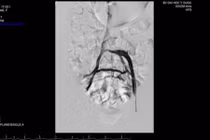

| Ảnh minh hoạ. |

Khi suy tĩnh mạch nông chi dưới mạn tính đã tiến triển đến các giai đoạn nặng, bệnh nhân cần được cân nhắc điều trị bởi các phương pháp can thiệp xâm lấn tối thiểu như can thiệp nhiệt nội mạch (sử dụng sóng có tần số radio hoặc sóng laser), tiêm xơ, hoặc phẫu thuật.